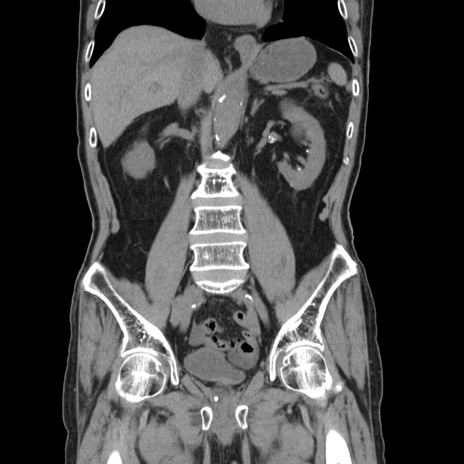

症例24(冠状断像)

【症例】80歳代男性

【主訴】左側腹部痛、嘔吐

【現病歴】本日早朝より左腹部に痛みあり。昼頃嘔吐認めたため、救急要請。

【既往歴】直腸癌(Mile手術)、胆摘

【身体所見】意識清明、BT 35.9℃、BP 221/93mmHg、SpO2 97%(RA) 、腹部:左ストーマ周囲に限局性の腹部膨隆あり。 膨隆部自発痛・圧痛あり・軟。

【データ】WBC 7700、CRP 0.09